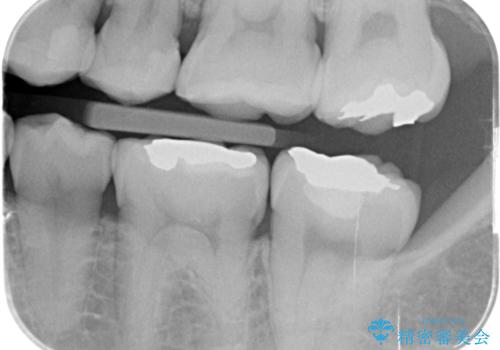

- 左下の銀歯の横から小さい虫歯になっていたため治療しました。

- 15.4万円(emaxインレー 7.7万円x2本)費用は治療当時の料金となります